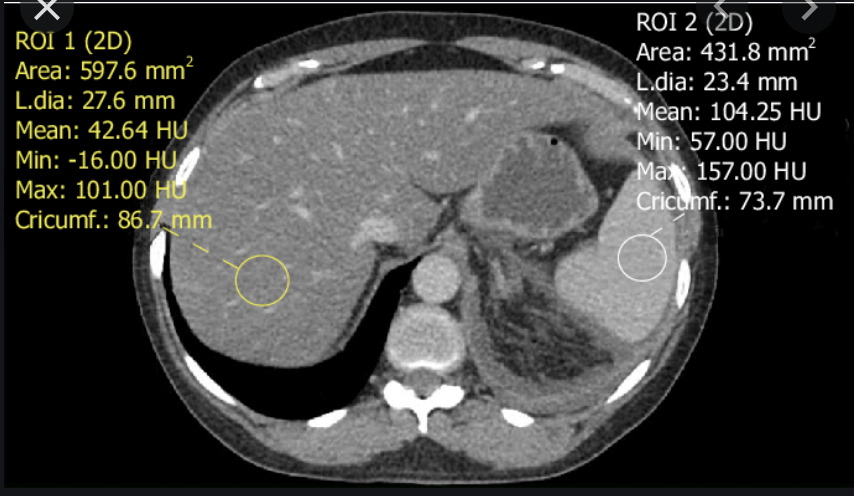

Ix: NCCT normal app of liver relative to spleen; HUs.

Ix: liver should be slightly hyperattenuating relative to spleen; normal liver 10HU < spleen.

Normal liver attenuation